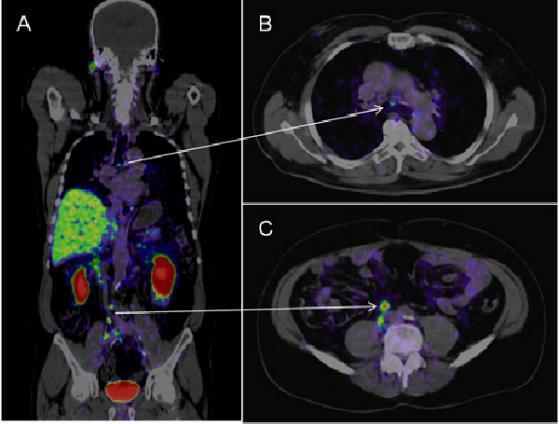

Prostate PET CT

PSMA (prostate-specific membrane antigen) / PET CT uses an isotope specific to the prostate, to accurately detect recurrence or spread of prostate cancer.